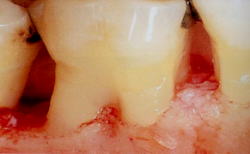

![]() |

麻酔下でのSRP後の歯肉からの出血は、臼歯部分岐部で多い |

根分岐部の歯石除去の困難性は、文献で証明されており、その結果、臼歯部分岐部は手術の可能性が高いことが示唆されます。

しかし、単根だと取り残しが少ないことが示されています。その結果、前歯・小臼歯部では、手術の可能性が低いことが示唆されます。